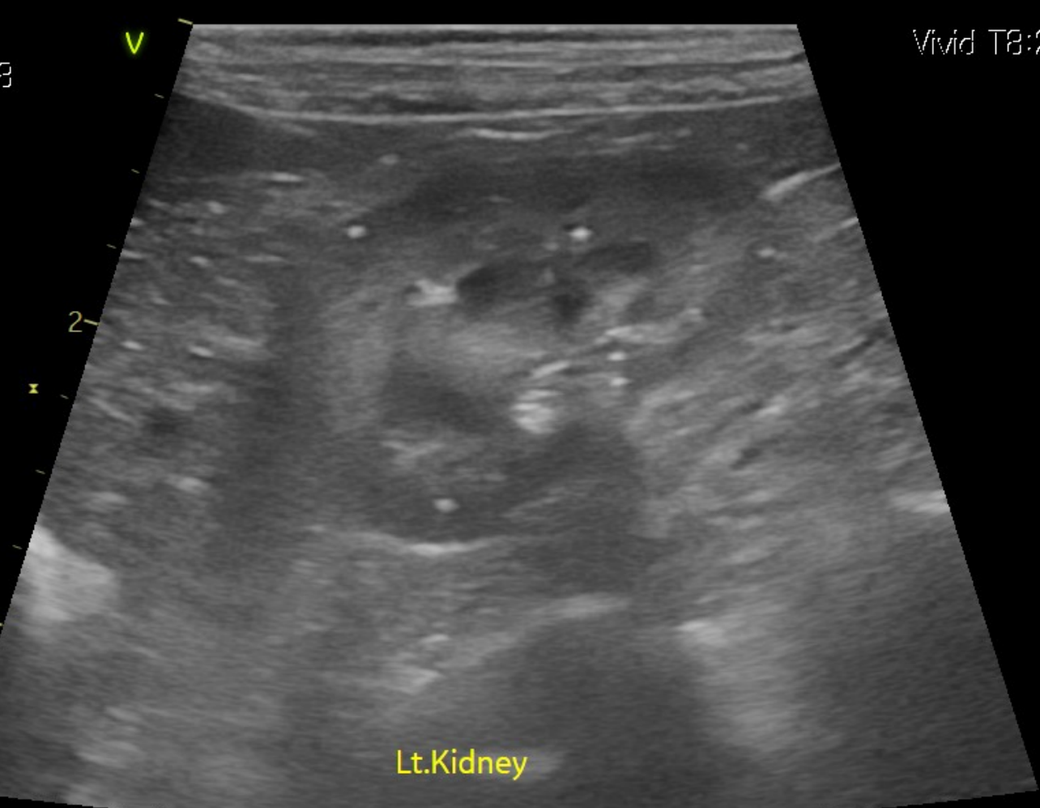

강아지 신장결석 종류 모양만으로는 판단이 안되나요? 소변에선 크리스탈이 발견된게 없다고 합니다

모양만으로 추측 조차 할수가 없는건가요? 한번 봐주시면 감사하겠습니다.

예, 없습니다. 결석이 매우 커진 상태 (몇센치미터 크기 정도)로 커졌을때나 일부 추정되지만 겉면과 내부 코어의 씨앗의 성분은 별도라 이때는 또 성분검사를 해야 하는정도로 부정확합니다.